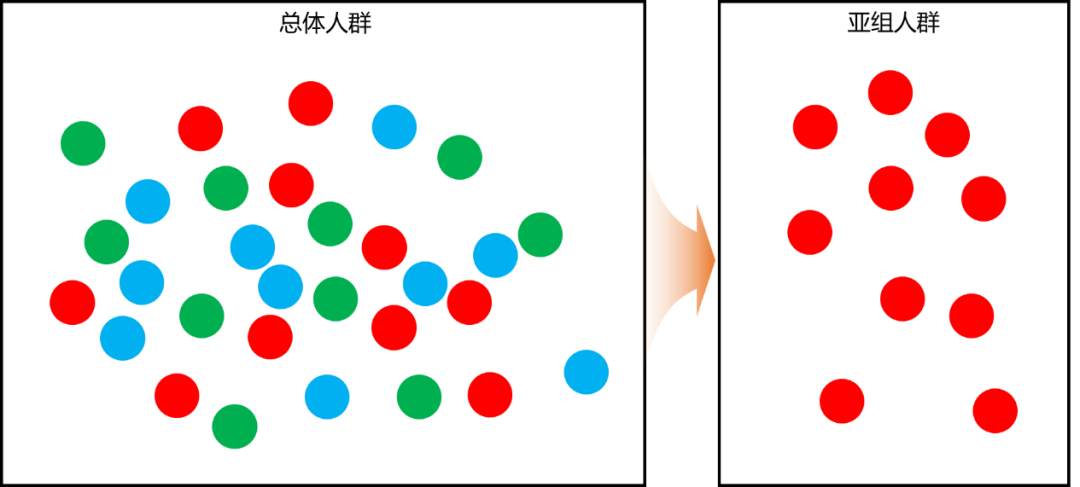

弥漫大B细胞淋巴瘤(DLBCL)是非霍奇金淋巴瘤(NHL)最常见的病理亚型。R-CHOP治疗方案虽然改善了患者的生存状况,但多数DLBCL仍预后较差,还有约40% DLBCL患者会出现疾病进展,后线缺乏标准治疗方案。且当患者合并多种疾病,一般状况较差时,如何选择后线治疗方案?本文的这一例应用新型BTK抑制剂治疗双表达DLBCL患者诊治经过,或为临床提供更多思考。 一81岁高龄患者3月余前无明显诱因下出现左侧季肋部为主胀痛,伴进食后上腹部不适。无恶心呕吐、无畏寒发热、无腹泻、无盗汗消瘦等。3月来患者症状反复,无明显缓解因素。患者1周前至我院门诊就诊,查腹部增强CT:1.左肝术后,肝内外胆管扩张,肝门部为主胆管壁厚强化、欠光整,结合病史,癌需考虑;2.左中腹壁外团块影,周围腹腔多发子灶、伴后腹膜多发肿大淋巴结,恶性肿瘤考虑;3.肝硬化,胆囊未见,双肾囊肿。动脉硬化;4.子宫附件未见。现为求进一步诊治,拟“腹部肿物”收住入院。 患者子宫肌瘤术后40余年。胆囊切除术后30余年。高血压病10余年。6年前左半肝及尾状叶切除术[胆管上皮异型增生,局灶癌变(高分化腺癌)]。 入院检查:神志清、精神可,全身皮肤未见明显黄染,浅表淋巴结未及肿大,双肺呼吸音清,未及干湿性啰音,心律齐,杂音未及,腹部稍膨隆,腹软,腹部可见陈旧性手术疤痕,腹部无明显压痛、反跳痛,墨菲氏征阴性,四肢肌力及肌张力可,病理征阴性。 相关辅助检查:心电图提示窦性心律,前壁轻度T波改变;血常规检查白细胞计数3.3×109/g,红细胞计数3.66×1012/g,血小板计数47×109/g,单核百分数13.6%,中性粒细胞百分数39.0%;乳酸脱氢酶269 IU/L;心脏彩超示室间基底段增厚,左房增大,轻度三尖瓣反流伴中度肺动脉高压,另有轻度二尖瓣、主动脉反流。 影像学检查:上腹部、盆腔增强示,左肝术后,肝内外胆管扩张,肝门部为主胆管壁厚强化、欠光整,结合病史,癌因考虑;左中腹壁外团块影,周围腹腔多发子灶,伴后腹膜多发肿大淋巴结,恶性肿瘤考虑;肝硬化,胆囊未见,双肾囊肿,动脉硬化;子宫附件未见。 超声检查:双侧乳房、腋下彩超检查,双乳超声未见明显异常;双侧腋下超声未见明显肿大淋巴结。 甲状腺彩超检查提示,甲状腺左叶术后,右叶多发结节,考虑结节性甲状腺肿;其中,中上极结节建议随访。 病理骨髓穿刺:骨髓有核细胞增生活跃,粒系占69.0%,红系21.0%,粒红比=3.29:1;粒系增生活跃;红系增生尚活跃;巨核细胞量减低,巨核细胞功能差,散在及成堆血小板少量可见;涂片未见淋巴瘤及其他特殊异常细胞。 病理检查,镜下示造血组织约占30%,粒系增生活跃,各阶段粒细胞均可见,以中晚幼及以下阶段细胞增生为主;红系增生活跃,有核红细胞散在分布,幼红细胞簇可见;巨核系增生活跃,数量及分布未见明显异常。 (腹腔肿物穿刺)弥漫大B细胞淋巴瘤,伴重度挤压伤。免疫组化A片:CK-pan(-)、CD20(+)、CD3(-)、Ki-67(高表达)、CD79a(+)、C-Myc(约40%+)、CD21(-)、CD10(-)、BCL-6(+)、MUM1(-)、BCL-2(-)、Cyclin D1(-)、CD5(局灶+)、TDT(-)、MYC-FISH(+)、BCL-6-FISH(+)。 诊断 非霍奇金淋巴瘤,弥漫大B细胞淋巴瘤 GCB亚型 II期A组 IPI评分3分。高血压病、低钾血症;子宫肌瘤术后、胆总管切开取石术后、左半肝及尾状叶切除术后、胆囊切除术后;结节性甲状腺肿。 2020.8.20开始,予R2+泽布替尼免疫靶向治疗:[国产]利妥昔单抗针553 mg 静脉滴注 QW*4dose,来那度胺25 mg 口服 每日一次 D1-21,泽布替尼160 mg 口服 每日两次。 复查CT提示,左腹肿块、左肾上腺结节、后腹膜淋巴结均较2020.7.30缩小。左膈抬高,左肝及胆囊术后,慢性胆管炎,双肾小囊肿,子宫术后,动脉壁钙化。疗效评价为,部分缓解(PR)。 2020.9.29复查CT提示,评估肿瘤较8.20缩小,疗效评估PR。因此予以ZR2继续治疗。 2020.11.29进一步复查腹部CT提示,淋巴瘤治疗后改变,左腹结节、左肾上腺小结节、后腹膜小结节较2020.9.29相仿。左膈抬高,左肝及胆囊术后,慢性胆管炎,双肾小囊肿,子宫术后,动脉硬化。疗效评价为,部分缓解(PR)。疗效评价为PR。 行R+泽布替尼方案进行治疗。治疗后无不适,予出院,约1月后入院行下一周期化疗。 本病例中的81岁高龄患者合并高血压、低钾血症、子宫肌瘤术后、胆总管切开取石术后、左半肝及尾状叶切除术后、胆囊切除术后等多种疾病,无法耐受化疗。曾予R2+泽布替尼治疗,达到PR。本次行R+泽布替尼为主的方案进行治疗。治疗期间,患者无明显不良反应,治疗效果可观,患者持续PR。 DLBCL存在很大的生物学异质性,其不同诊断类型,往往直接关系到临床治疗效果及患者生存期。 随着以利妥昔单抗等免疫药物的出现,DLBCL治疗水平得到了极大提升,但仍有40%的患者在标准R-CHOP一线治疗后无法治愈,会进展为复发/难治DLBCL。值得一提的是,无法治愈的患者多为特殊类型DLBCL,且常伴有预后不良因素。多项研究表明,BTK抑制剂在某些特定类型DLBCL的治疗中显示出了一定疗效的获益。 如该病例中,患者年龄较大,且病史复杂,合并高血压、低钾血症,并史,并进行过子宫、胆总管切开取石术、左半肝及尾状叶切除、胆囊切除等手术,经过充分考虑,予患者利妥昔单抗及进行了创新性结构改造的新一代BTK抑制剂泽布替尼。泽布替尼对BTK靶点特异性更高、脱靶效应更低,并拥有更优的药代动力学效应。2017年ASH-AU003研究表明,泽布替尼单药治疗DLBCL的ORR达31%。此外,BTKi口服给药,用药方便,靶点抑制精准,3/4级不良事件较少,单药疗效相对稳定,联合治疗也不影响CD20的ADCC作用。现有数据表明,新一代BTKi抑制剂泽布替尼对于部分淋巴瘤疗效更佳。 而在该病例的治疗中,这一结果也得到了证实。我们有理由相信,我国原来越多的原研药物将承载着广大临床医生和患者的希望,让更高效、更低毒性的治疗方案成为现实,切实造福我国乃至世界范围内更多的淋巴瘤患者! 关于泽布替尼: 泽布替尼是由我国百济神州公司自主研发的新一代强效BTK抑制剂。泽布替尼通过创新、优化的分子结构,对BTK靶点选择性更强且脱靶效应更低,可最大程度提高BTK占有率并最小化脱靶作用,从而特异性地减少治疗过程中不良事件的发生。基础研究表明,使用泽布替尼后在外周血和淋巴结中均可观察到完全持久的BTK占有。 泽布替尼自2012年6月正式立项研发,如今在全球的临床试验中,包括慢性淋巴细胞白血病/小淋巴细胞淋巴瘤(CLL/SLL)、套细胞淋巴瘤(MCL)、华氏巨球蛋白血症(WM)、滤泡性淋巴瘤(FL)等,泽布替尼均表现出更高的有效性和安全性。 2019年11月15日,泽布替尼以“突破性疗法”的身份被美国FDA以快速通道资格审批上市,用于既往至少接受过一种治疗的成年MCL患者,打破了中国抗癌新药“只进不出”的历史。2020年6月3日,泽布替尼(百悦泽®)获中国国家药品监督管理局批准,在中国上市。本次入院详情

思考与体会